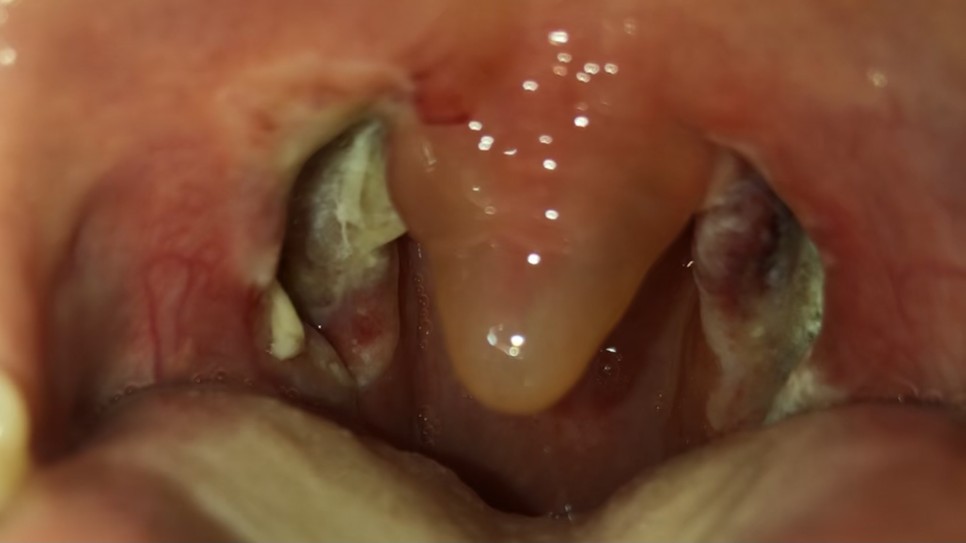

마지막으로 편도사진 보여드리는데 너무 징그러워요.

못 보시는 분들은 뒤로 간다!

수술 전

수술 당일

수술 1일째

수술 이틀째

원래 편도선이 정말 컸죠?쿠쿠ㅜㅜ의사가 왼쪽 편도선은 잘 뜯겼지만 오른쪽 편도선은 주변과 유착이 심해서 조금 고생했어요 ㅠㅠ

제가 왜 계속 목젖 얘기를 했는지 이해가 되세요?ㅠㅠ갈증이 정말 커졌습니다.

시간이 지날수록 편도로 백배?이점이 생겨서 나중에 다시 떨어진답니다!

그 사람 때문인지 입냄새가 좀 나요… (´;ω;`)